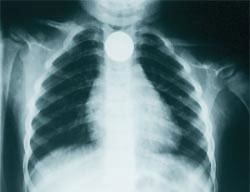

La importancia de esta recomendación la veréis claramente cuando experimentéis, al igual que yo, los escalofríos que produce la visión de estas radiografías realizadas a bebés de entre siete meses y dos años. Pilas, tornillos, monedas, imperdibles... ¡nunca antes los había visto a través de rayos x! Seamos conscientes de los peligros que rodean a nuestros pequeños y brindémosles la seguridad de un hogar en el que jugar y aprender.

Una moneda

Un tornillo

Un imperdible

Unas pilas